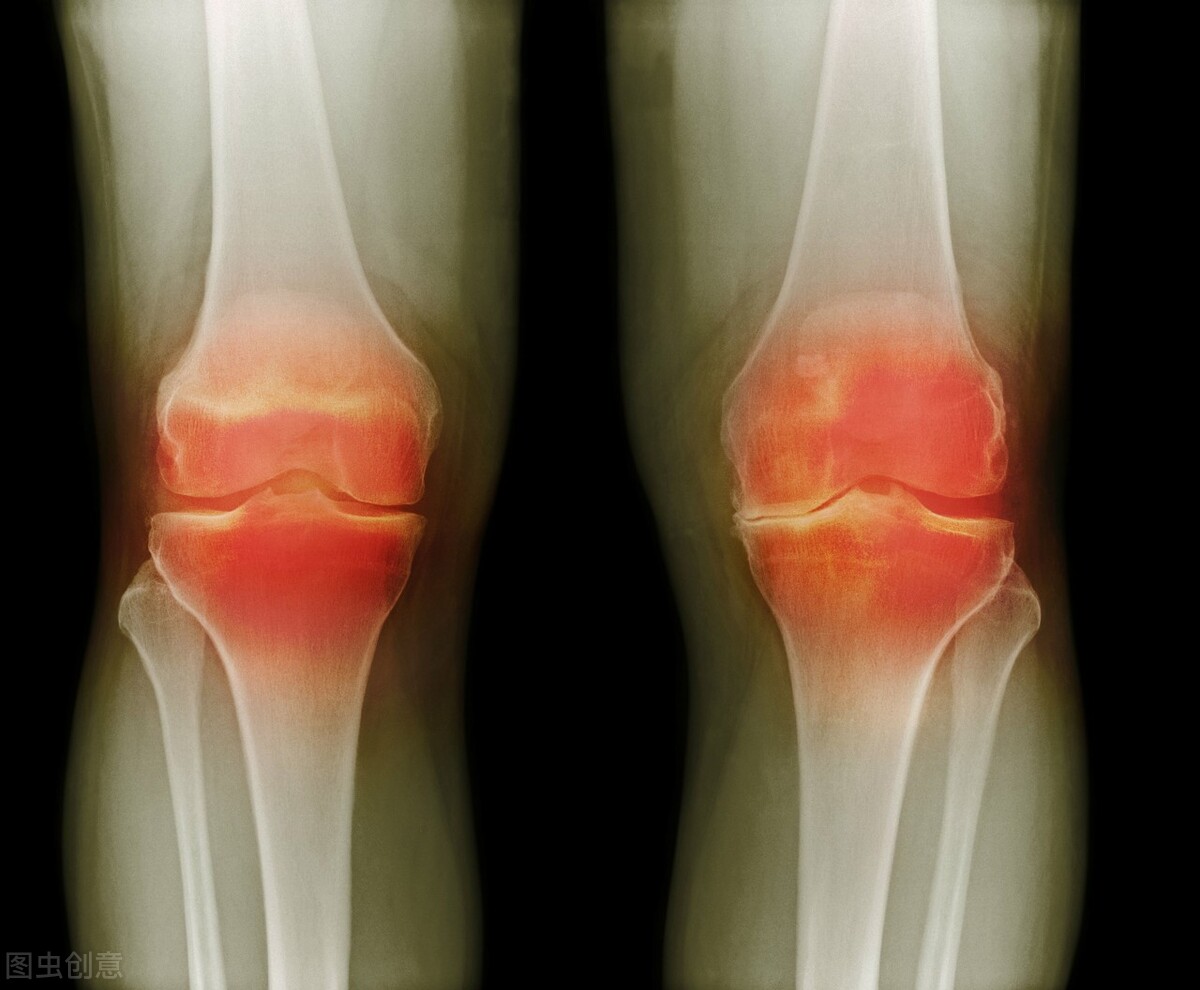

滑膜遭受刺激 , 出现炎症 , 表现为滑膜的增生或者是滑膜积液大量产生 , 被称作滑膜炎 。 膝关节作为全身最重要的关节 , 也是滑膜最多的关节 , 因此容易出现滑膜炎 , 老百姓俗称膝盖滑膜炎 。 一旦患上滑膜炎 , 就会出现膝盖疼痛、关节肿胀以及生理活动受阻的表现 , 局部会发热红肿 。 如果不及时进行正规的治疗就会逐渐加重骨与骨之间的摩擦 , 损伤 。